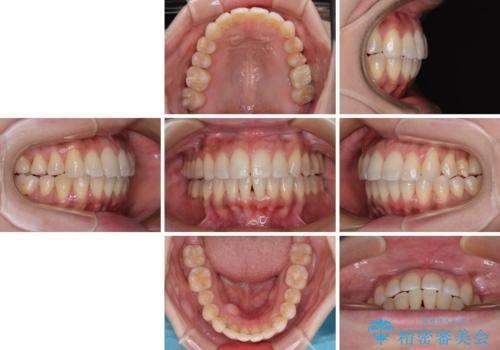

歯の傾斜が改善され、インプラントによるクラウンが装着されたことで、物が挟まることもなくなりました。